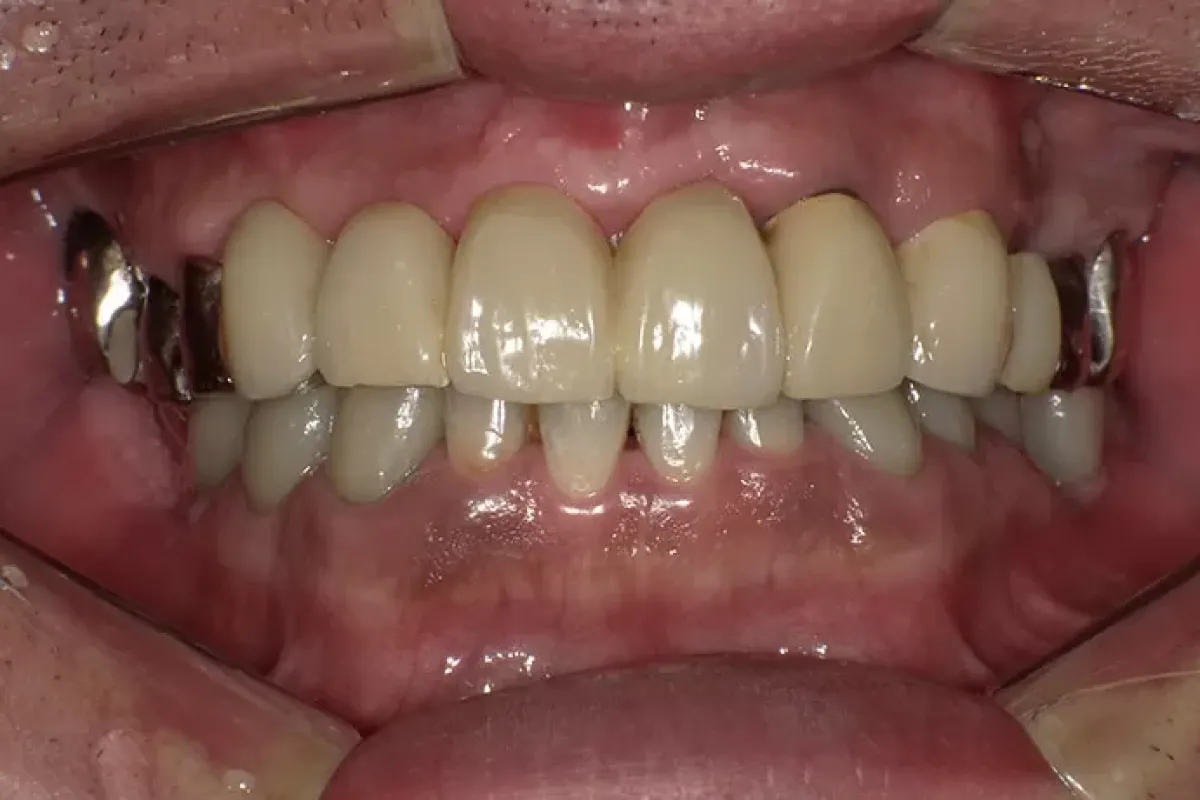

患者様情報 60代女性 患者様のお悩み 被せものがはずれた、前歯のブリッジがぐらぐらする 治療概要 虫歯治療、詰め物・被せ物、インプラント 提案内容 奥歯は金属修復補綴物の劣化、隙間からの虫歯があったので治 […]